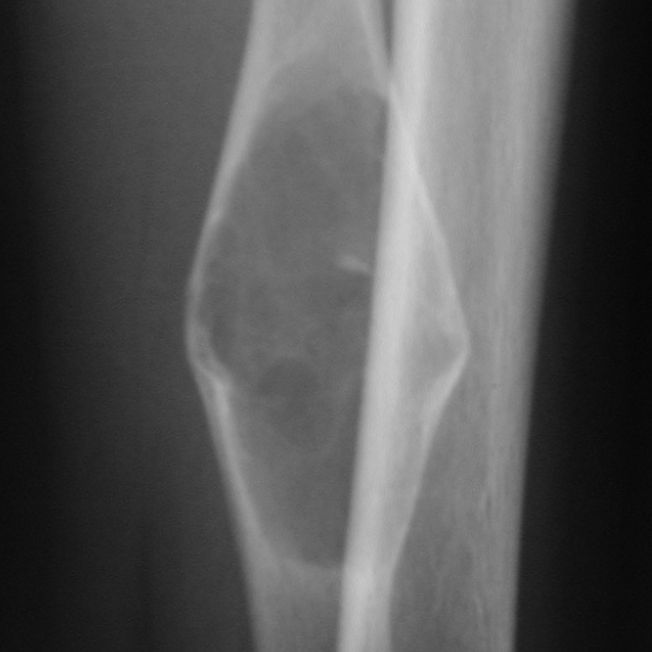

In questi casi ci troviamo di fronte a una frattura patologica su cisti ossee; anche in questi casi il reperto è occasionale dopo un trauma minimo accidentale. Possono riscontrarsi in varie parti del corpo, normalmente a carico delle ossa lunghe quali omero ( immagine a lato)  oppure in sede peroneale ( caso in basso ).